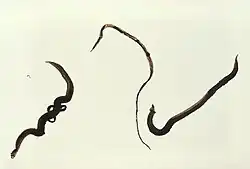

Heces

La identificación de los huevos en heces y/o en orina mediante técnicas de microscopía es el método de diagnóstico más práctico, siendo la unidad de medida el número de huevos por gramo de heces u orina. Ante sospecha de S. mansoni o S. japonicum es preferible el examen en heces, y ante sospecha de S. haematobium es preferible el examen en orina. Los huevos de S. haematobium son elipsoidales con una espina terminal; los de S. mansoni son elipsoidales, pero con la espina lateral; y los de S. japonicum son esféricos con un pequeño espéculo saliente.